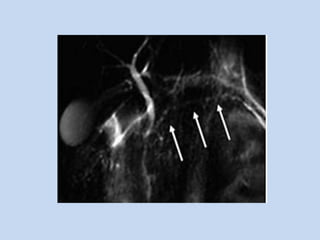

• In Primary Sclerosing Cholangitis :

characterize PSC – mural irregularities, strictures

& diverticular outpouchings.

- Conventional abdominal MR + MRCP provides

& portal hypertension in PSC patients.

APPLICATIONS • In PrimarySclerosing Cholangitis : - MRCP depicts the subtle ductal abnormalities that characterize PSC – mural irregularities, strictures & diverticular outpouchings. - Conventional abdominal MR + MRCP provides useful information regarding the presence of cirrhosis & portal hypertension in PSC patients.